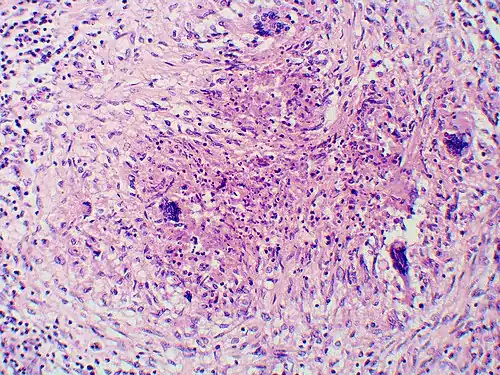

-

Granuloma with early suppuration. The fungal organisms are difficult to recognize at this low magnification.